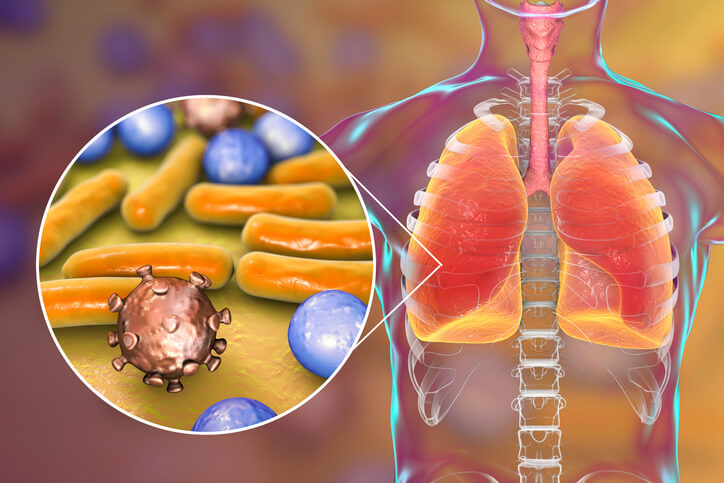

Фотографии бактерий, вызывающих бактериальные пневмонии у животных

Раздел: Другие животные